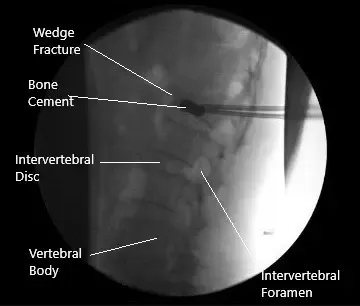

Imagen fluoroscópica intraoperatoria de la cifoplastia.

Una vez que encontramos las agujas Jamshidi en su posición adecuada, se retiraron las agujas Jamshidi. Las mangas se retiraban aproximadamente un centímetro y se insertaban globos a ambos lados. Los globos estaban inflados. Sentimos que había una brecha en la placa inferior del lado derecho, así que la inflación se detuvo en ese momento.

Se mezclaba cemento óseo e insertaba en los lados derecho e izquierdo. Se podían insertar unos 4 cc de cemento. Se sospechaba una ruptura en la placa inferior del extremo, pero el cemento seguía en el cuerpo vertebral. Los tamps se metieron en las mangas hasta que el cemento se endureció. Se quitaron las mangas. La foto final se tomó en la vista AP y lateral y se guardó. La herida fue completamente lavada.